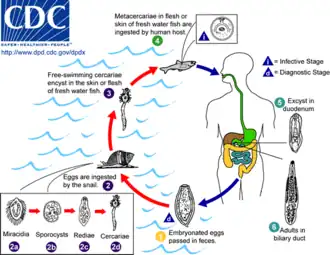

Certain parasitic liver diseases may be risk factors as well. Colonization with the liver flukes Opisthorchis viverrini (found in Thailand, Laos PDR, and Vietnam)[18][19][20] or Clonorchis sinensis (found in China, Taiwan, eastern Russia, Korea, and Vietnam)[21][22] has been associated with the development of cholangiocarcinoma. Control programs (Integrated Opisthorchiasis Control Program) aimed at discouraging the consumption of raw and undercooked food have been successful at reducing the incidence of cholangiocarcinoma in some countries.[23] People with chronic liver disease, whether in the form of viral hepatitis (e.g. hepatitis B or hepatitis C),[24][25][26] alcoholic liver disease, or cirrhosis of the liver due to other causes, are at significantly increased risk of cholangiocarcinoma.[27][28] HIV infection was also identified in one study as a potential risk factor for cholangiocarcinoma, although it was unclear whether HIV itself or other correlated and confounding factors (e.g. hepatitis C infection) were responsible for the association.[27]